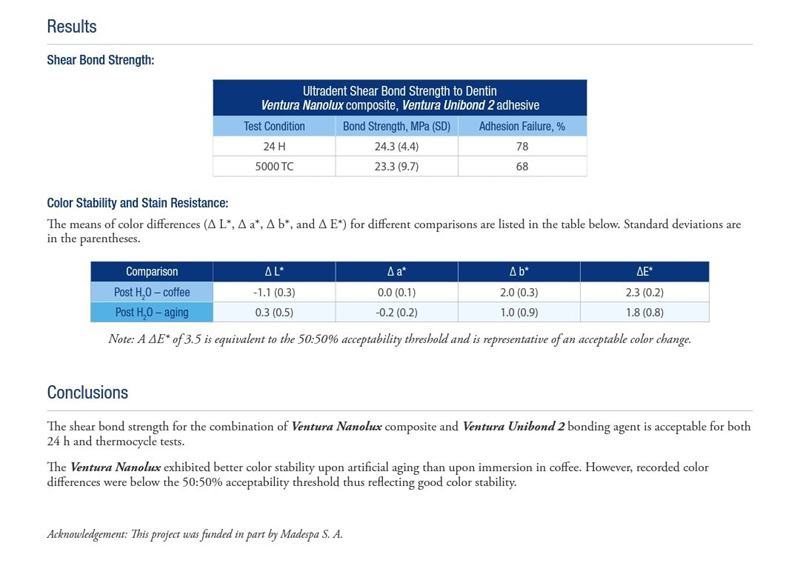

RAPORT BADAWCZY DAMICROBIOLOGY - VENTURA NANOLUX

Napisała Katarzyna SiekluckaVERNTURA NANOLUX to uniwersalny kompozyt, który reprezentuje estetykę, zachowanie połysku , odporność na przebarwienia i wysoką wytrzymałość. Siła wiązania, ścierania, stabilność kolorów i odporność na plamę kompozytową.

Zdjęcie 1

-

Zdjęcie 2